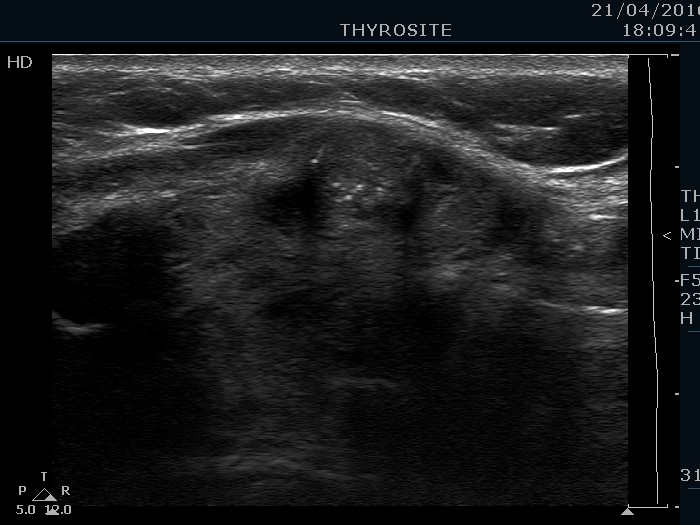

Ultrasonography. The thyroid was echonormal and contained hypoechogenic areas. The echogenicity index was around 20%. There was a moderately hypoechogenic lesion presenting microcalcifications in the ventral part of the right lobe.